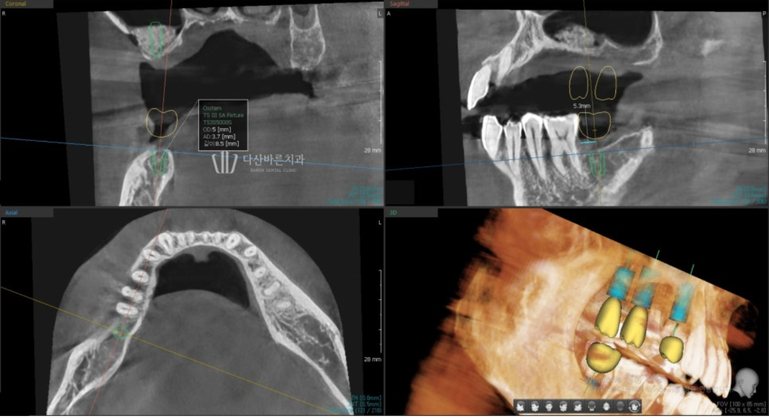

Dựa trên dữ liệu thu được một cuộc phẫu thuật mô phỏng sẽ được thực hiện bằng kỹ thuật số.

Sau khi phân tích vị trí tối ưu để implant được sử dụng lâu nhất và bền nhất,

chúng tôi hầu như cấy trước implant vào vị trí đó.

Trong quá trình này, chúng tôi không chỉ lập kế hoạch về góc và vị trí đặt implant

tối ưu mà còn xem xét nhiều khía cạnh khác nhau để đảm bảo không có vấn đề hoặc tác dụng phụ như dự kiến.

Lập kế hoạch vị trí và góc đặt implant tối ưu

Lên kế hoạch đặt trụ implant tránh dây thần kinh hàm dưới

Ngoài ra, vị trí chính xác của dây thần kinh

chỉ có thể được xác định bằng dữ liệu 3D.

Thông qua đó, chiều dài và góc của mô cấy có thể

được điều chỉnh để tránh chạm vào dây thần kinh trong quá trình phẫu thuật,

từ đó ngăn ngừa các tác dụng phụ như tổn thương dây thần kinh.

Sau khi xem xét tính ổn định của phẫu thuật thông qua phẫu thuật

mô phỏng trên máy tính, vị trí đặt cuối cùng sẽ được xác định.

Sau khi ghép xương, vị trí và góc đặt implant được lên kế hoạch thông qua quy trình mô phỏng.

Ảnh trên là ảnh chụp quá trình cấy ghép implant mô phỏng.

Với bức ảnh này, bạn có thể kiểm tra trước độ dày của xương

có đủ hay không khi trụ implant (vít, vật cố định) nằm bên trong xương nướu,

sau đó đặt trụ implant ở vị trí và góc chính xác hơn.

Sau khi điều chỉnh khớp cắn và độ thẳng hàng giữa răng trên và răng dưới,

hướng dẫn phẫu thuật kỹ thuật số cuối cùng được tạo ra dựa trên các chi tiết phẫu thuật đã được lên kế hoạch.